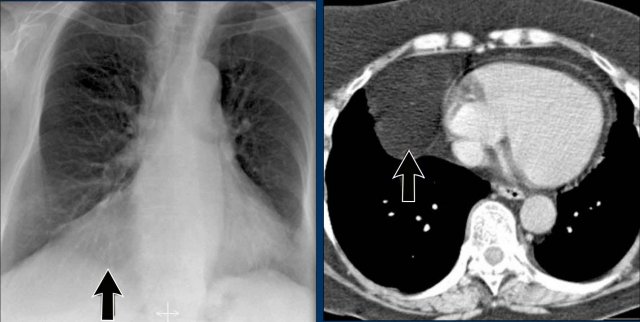

Hidden Areas (3): Pneumonia Below the Diaphragm

In this case, a pneumonia was primarily located below the right diaphragmatic dome (yellow arrow), within the posterior basal segment of the right lower lobe.

• On the lateral view, there is an increase in opacity over the lower thoracic vertebrae, indicating lower lobe consolidation (arrow).

• Again, image magnification may be necessary for adequate assessment.